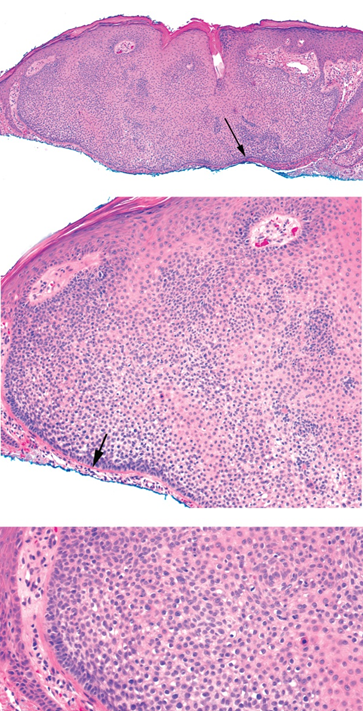

Rosai Dorfman

Fibrotic nodules showing light and dark areas

Sheets of histiocytes (light areas) with nodules of lymphoytes (dark areas)

Emperipolesis (intact cells, especially lymphocytes and plasma cells, passing through histiocytes)

S100 positive, CD1a negative, CD68 positive